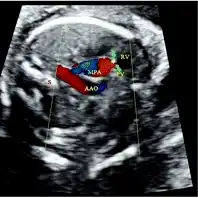

Doppler resolved this problem by visualizing the retrograde flow in the MPA , indicating pulmonary valve atresia -

Ventricular septal defect via echocardiogram